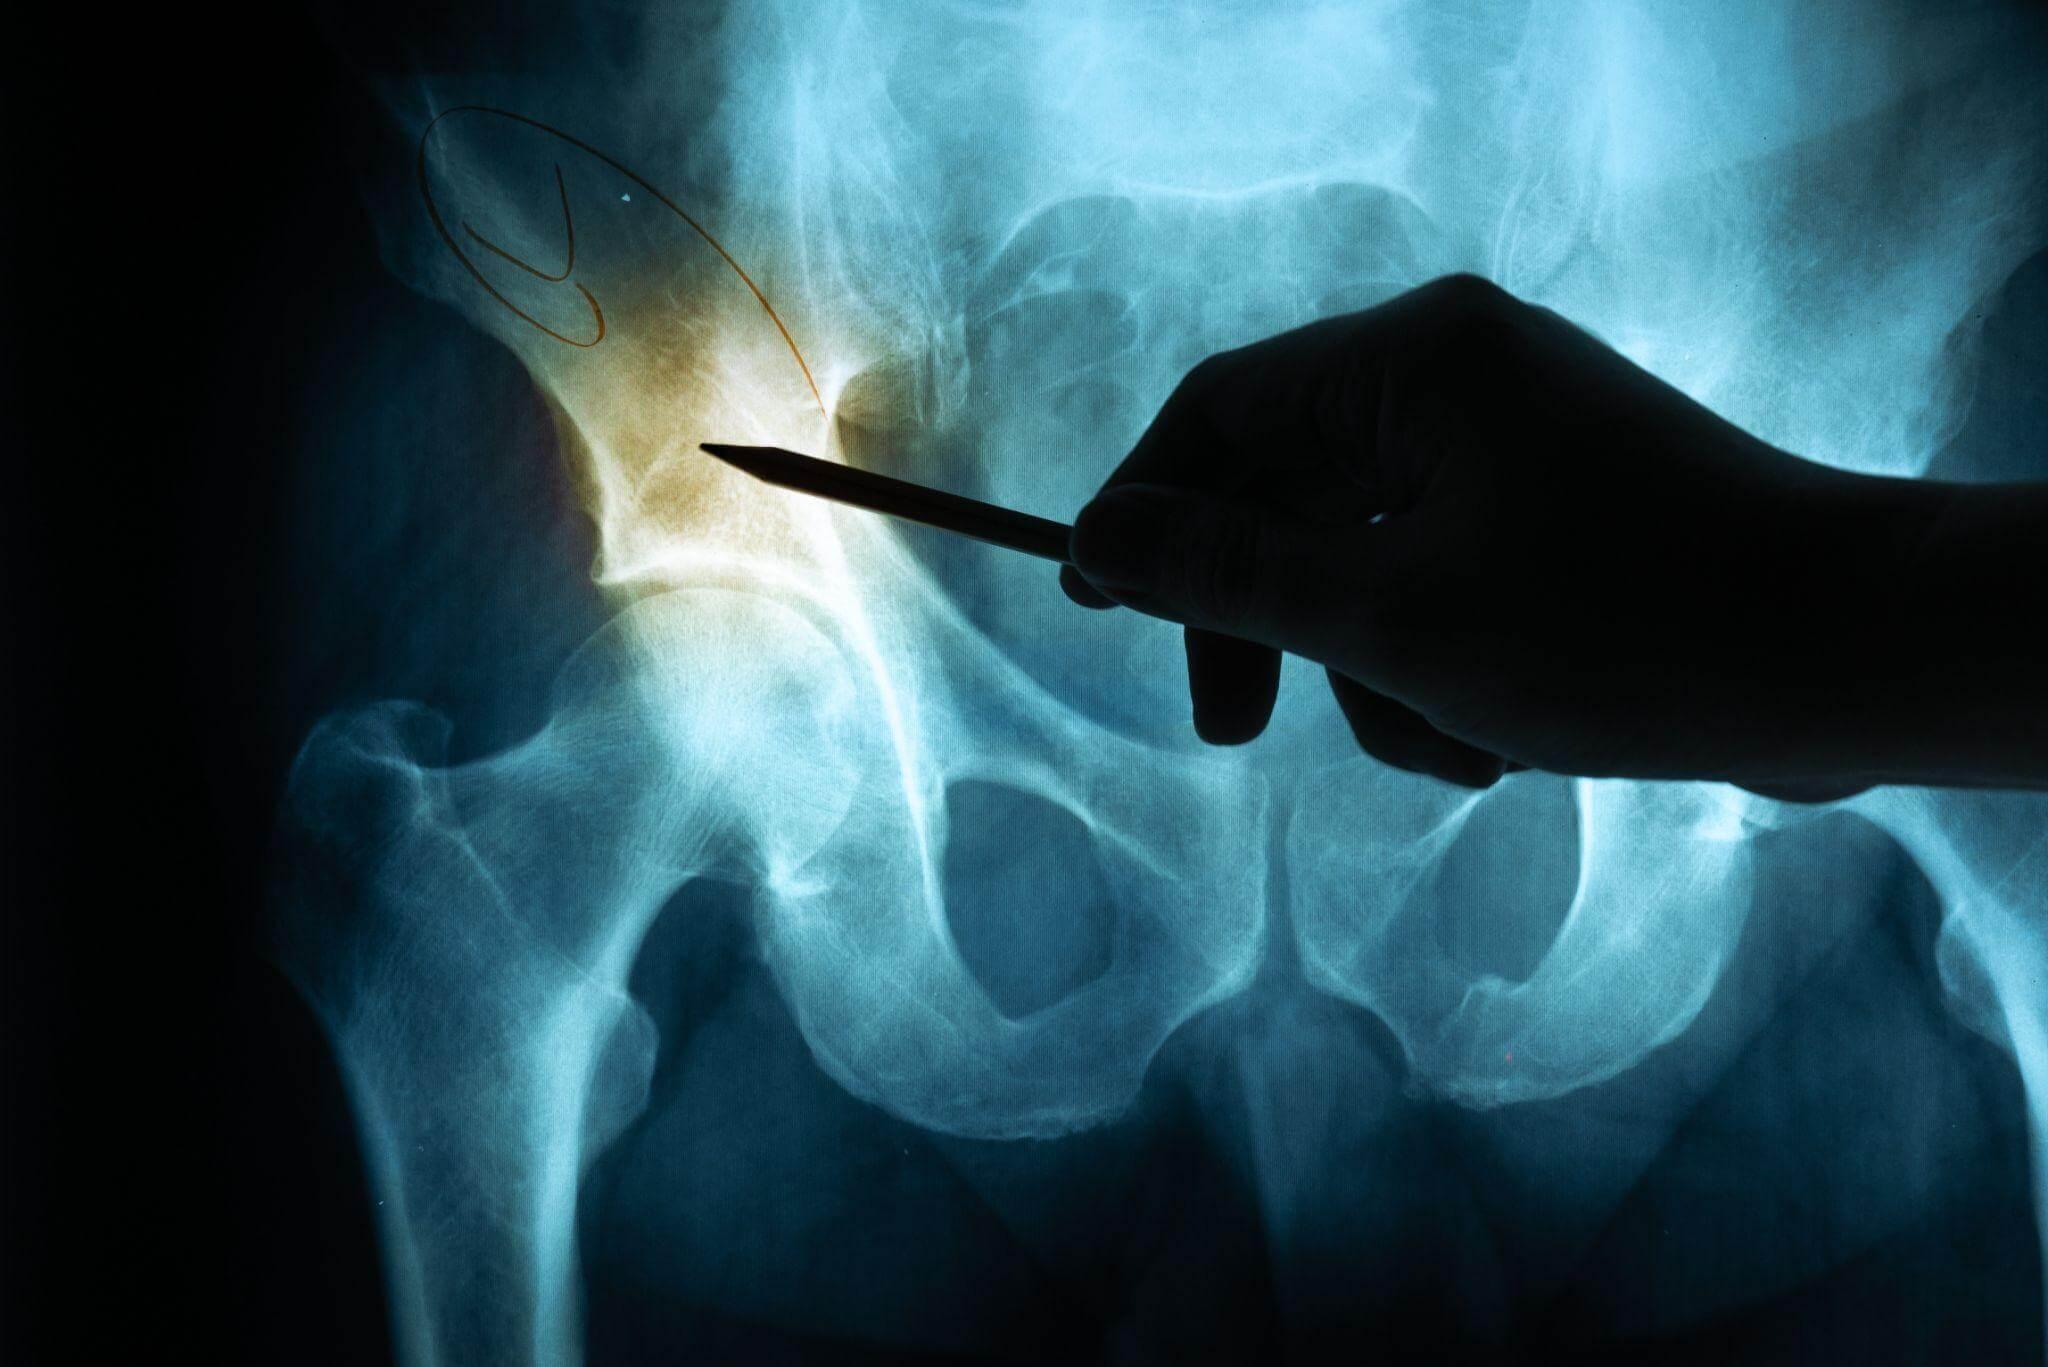

Diagnosis of Hip Pain After a Car Accident

If you report hip pain after an accident, doctors will usually start with a physical examination to check for tenderness, swelling, or limited movement. Imaging tests, such as X-rays, MRIs, or CT scans, may be ordered to identify fractures or joint damage. Warning signs like severe pain while walking, visible bruising, or difficulty bearing weight should be taken seriously.